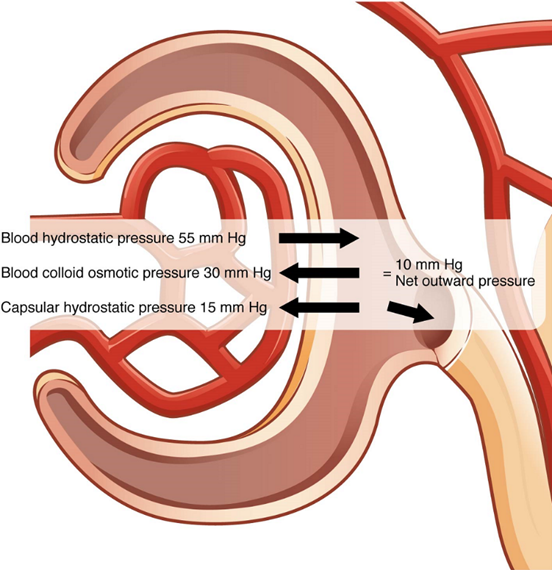

Filtration

The volume of filtrate formed by both kidneys per minute is termed the glomerular filtration rate (GFR). The heart pumps about 5 L blood per min under resting conditions. Approximately 20 percent or one litre enters the kidneys to be filtered. Ninety-nine percent of this filtrate is returned to the circulation by reabsorption so that only about 1–2 litres of urine are produced per day. The glomerular filtration rate is influenced by the hydrostatic pressure and colloid osmotic pressure on either side of the capillary membrane of the glomerulus (Figure 8). Filtration occurs as pressure forces fluid and solutes through a semipermeable barrier with the solute movement constrained by particle size. Hydrostatic pressure is the pressure produced by a fluid against a surface. If you have a fluid on both sides of a barrier, both fluids exert a pressure in opposing directions. Net fluid movement will be in the direction of the lower pressure.